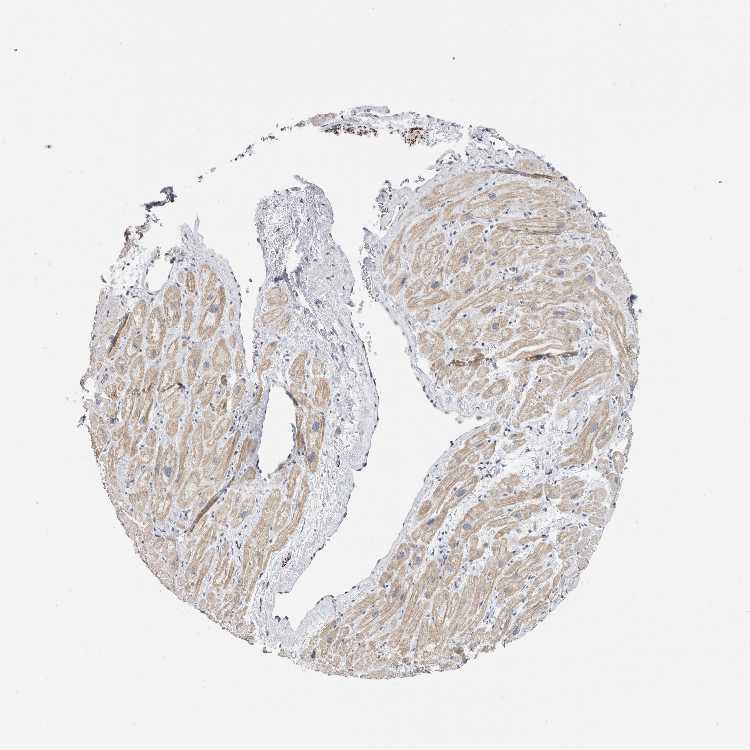

NEFM